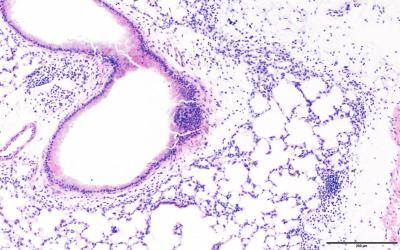

Researchers report that compared with mice exposed to filtered air in utero, mice exposed to ultrafine particles (UFP) in utero failed to develop strong immune responses to house dust-mite allergens, and at four weeks old, had less bronchiole inflammation and fewer white blood cells in their bronchoalveolar lavage fluid; this immune suppression was more pronounced in a mouse strain sensitive to oxidative stress, indicating that maternal oxidative stress responses to UFP exposure may alter fetal immune development, and in utero UFP exposure may predispose neonates to respiratory infections.

Article #18-16103: "In utero ultrafine particulate matter exposure causes offspring pulmonary immunosuppression," by Kristal A. Rychlik et al.